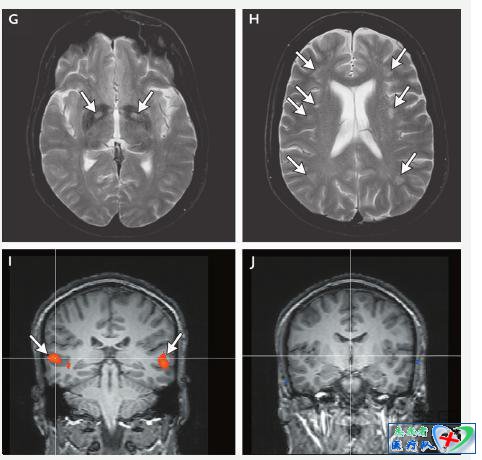

患者一氧化碳中毒后的脑磁共振成像(MRI)检查(为了研究目的而实施,某些病例有施行MRI的临床适应证,例如为了除外与一氧化碳暴露无关的疾病),有可能显示异常结果(图3)。在一项纳入一氧化碳中毒患者的前瞻性研究中,脑MRI显示(患者的)T2加权高信号数,多于基准数据库中的高信号数。虽然影像学异常改变的发生率还不知道,但其他纳入一氧化碳中毒患者的研究曾经报告过中毒数年后的基底神经节病变、海马和其他结构萎缩,以及中毒1个月后扩散张量成像的异常结果。然而,这些异常对一氧化碳中毒而言都不具有特异性。